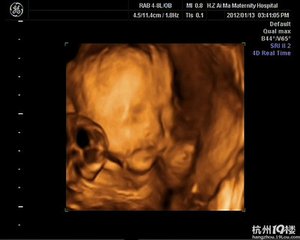

妊娠是一个复杂的过程,从卵子受精到发育成熟,每个孕周的情况都会有差异。孕妇B超检查可清楚地看到胎儿较大器官的形态,胎儿活动状况、羊水量、胎盘形态及位置等情况,B超检查是孕检的重要内容。可是,b超单怎么看,却是让孕妇苦恼的事情。准妈妈拿着B超单到医生面前很急切地问:医生,帮我看看这张单的结果怎样。医生拿过来后,往往扫一眼后就说:没事,正常。

孕妇超声检查报告单一般包括以下几方面内容:胎囊、胎头、胎心、胎动、胎盘、股骨、羊水和脊柱。